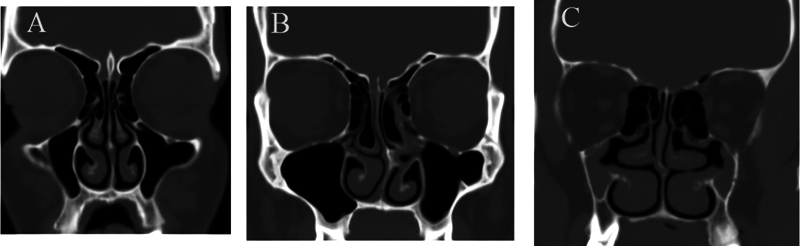

钩突(uncinate process, UP)是口鼻道复合体和中道中最重要和不变的标志。目的利用计算机断层扫描(CT)识别未发表的UP变异,并对其进行分类。方法对110例(220侧)旁鼻部CT进行扫描。轴向图像通过多平面重新格式化获得,以捕捉其他平面的精细细节。结果120例(220侧)CT扫描中,1型UP占84.5%,2型UP占12.3%,3型UP占3.2%,性别差异无统计学意义;中位UP占81.9%,垂直UP占16.3%,侧位UP占0.9%,缺失UP占0.9%,性别差异无统计学意义。总计8.63%的UPs采用了气动方式。结论本研究提高了外科医生和放射科医生对UP的认识,同时创建了一个标准的分类和描述,作为耳鼻喉科医生和放射科医生之间的共同语言,也可用于培训。

Introduction  The uncinate process (UP) is the most important and constant landmark in the ostiomeatal complex and the middle meatus. Objective  To identify the UP variations that have not been published before and establish a categorization using computed tomography (CT). Methods  The current study was carried out on 110 paranasal CT scans (220 sides). Axial images were acquired with multiplanar reformats to capture delicate details in other planes. Results  Out of 120 CT scans (220 sides), the UP was found to be of type 1 in 84.5%, type 2 in 12.3%, and type 3 in 3.2%, without significant diferences between genders, and it was found to be medialized in 81.9%, vertical in 16.3%, lateralized in 0.9%, and absent in 0.9%, without significant differences between genders. A total of 8.63% of the UPs were pneumatized. Conclusion  The present study improves surgeons' and radiologists' knowledge of the UP, while creating a standard classification and description to be used as a common language between otorhinolaryngologists and radiologists, which could also be used for training.